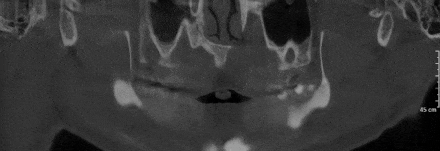

“伯爵Bondream”智能3D全景CBCT 多金屬去偽影圖

普通CBCT 多金屬去偽影圖(同一患者)

上頜竇底,骨小梁與下頜神經(jīng)管清晰可見(jiàn)

植體周圍無(wú)陰影,植體螺紋清晰可見(jiàn)